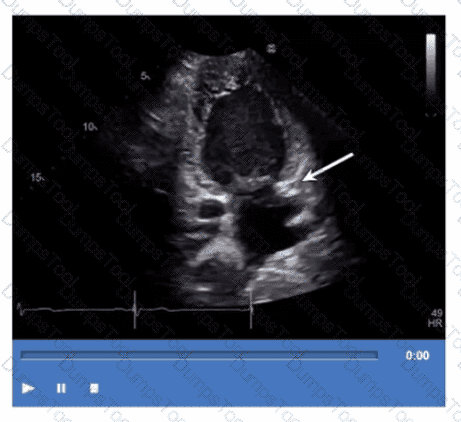

Which congenital abnormality is most consistent with the findings in this video?

Which step is next in further evaluation of the abnormality shown in this video?